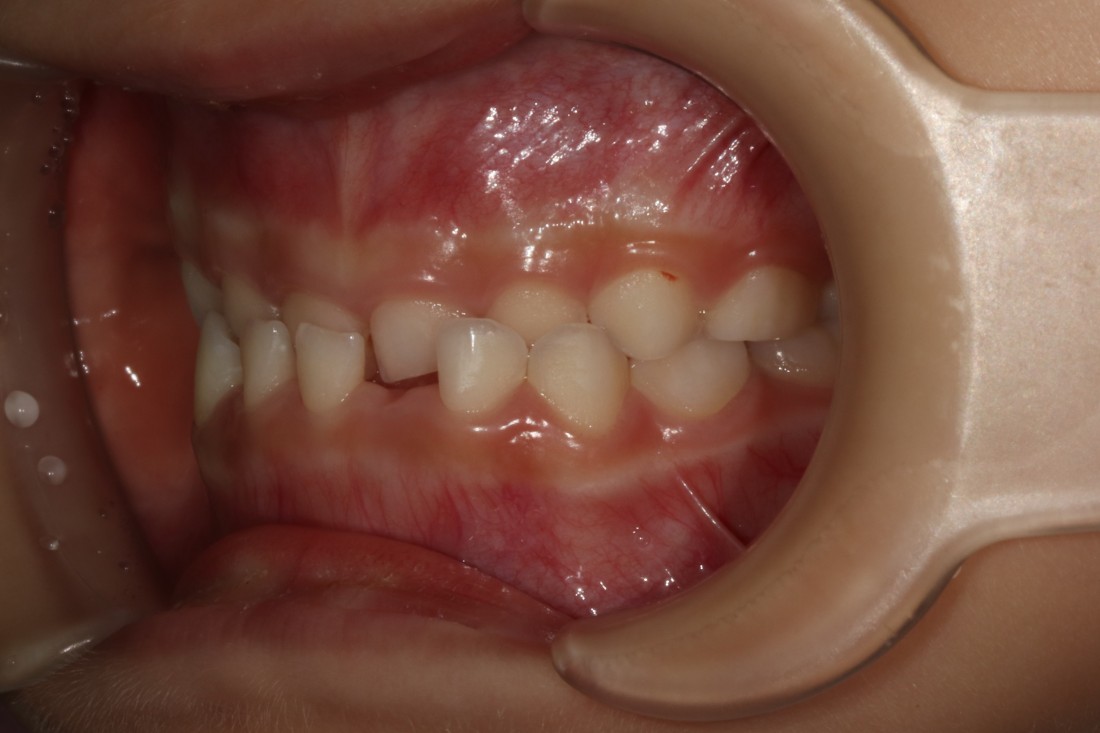

혹시 우리아이 치아가

이렇게 윗니보다 아랫니가 앞으로 나오며

맞물리고 있는 반대교합처럼 보이시나요?